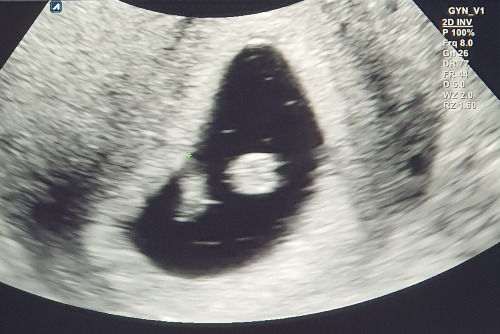

오늘 병원에서 두 번째 진료를 받고 왔어요.

아기 형태를 보고 아기 심장소리를 들었어요.

아기는 너무 조그맣고 희미한데 심장이 쿵쿵 뛰네요.

신기해라. 눈물이 펑펑 났어요.

저희 아기 보여드리며 마칩니다.

혹시 아주 잠깐의 시간이 있으시다면, 아기가 건강하고 튼튼하게 잘 자랄 수 있길, 그리고 세상의 사랑을 받고 감동을 주는 삶을 살길 함께 기도해 주세요. 저는 용기 있는 엄마가 되겠습니다.